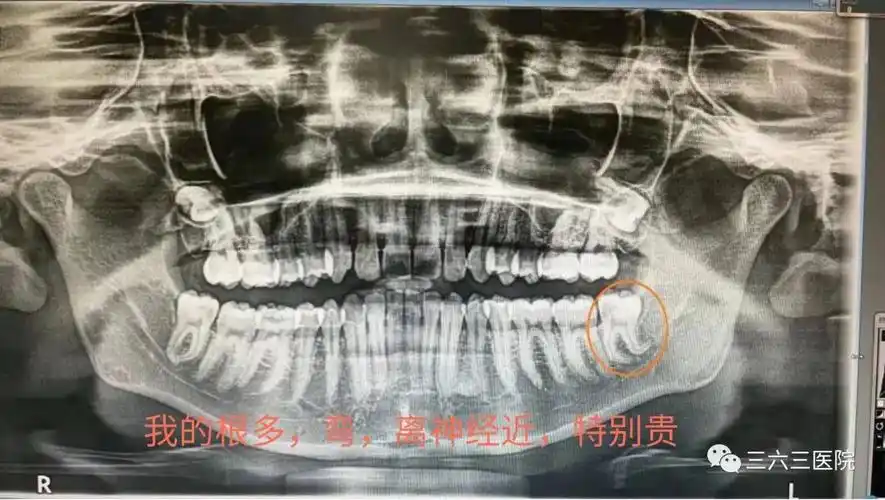

口腔科主治医师赵剑通过口腔全景片发现,沈先生不但长了4颗智齿,其中2

拍摄"全景片",有时还会拍摄口腔cbct,预估智齿的位置,牙根数目及形态